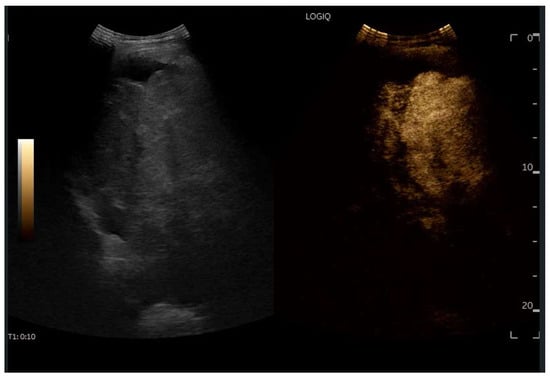

CEUS is valuable for characterizing the contrast enhancement patterns of liver nodules [68,69,70,71]. In Europe, the US contrast agent SonoVue® (sulfur hexafluoride; Bracco, Milan, Italy) is approved only for intravenous applications in patients over 18 years of age [72]. CEUS use in Fontan patients remains limited due to their frequent collateral circulation with right-to-left shunts, which is considered a contraindication in Europe but not in the United States. Beyond structural liver changes, CEUS reveals markedly heterogeneous hepatic enhancement with mosaic or reticular patterns, mainly due to slow and reduced enhancement near congested hepatic veins—one of the most common imaging features of FALD [54,73]. Anecdotal experience suggests that CEUS demonstrates heterogeneous and decreased liver enhancement in the portal venous phase, similar to cirrhosis of other etiologies (Figure 14, Figure 15). Abnormal enhancement is more prominent at the liver periphery than centrally, while the hypertrophic caudate lobe often shows more homogeneous enhancement. In patients with FALD, the altered hemodynamics resulting from chronic hepatic venous congestion and low cardiac output can significantly influence CEUS dynamics. Despite these circulatory changes, CEUS in FALD generally preserves the standard temporal enhancement pattern. The hepatic veins, although congested, do not typically show early enhancement, as microbubble distribution primarily reflects arterial input. The systemic hypokinetic circulation characteristic of FALD may lead to delayed arterial arrival times and a prolonged transit of contrast, especially in the background of the liver. Nonetheless, FNH-like nodules frequently exhibit intense and early arterial-phase hyperenhancement, suggesting preserved or increased arterial supply in these lesions. This contrast behavior is essential for lesion characterization.

Figure 14.

Contrast-enhanced ultrasound (CEUS) in the late phase shows the appearance of hypo-vascular areas due to varying degrees of congestion and hepatic alteration. These areas may mimic malignant nodular lesions with early washout.

Figure 15.

CEUS exam showing late heterogeneous enhancement in the arterial phase with evidence of hypo-enhanced areas, thus mimicking a malignant wash-out.

CEUS plays a crucial role in evaluating hepatic nodules in FALD and Figure 16 (Figure 17). In non-cardiac cirrhosis, contrast washout in the late phase is highly indicative of HCC. However, in FALD and other congestive hepatopathies like Budd–Chiari syndrome, FNH-like nodules can also exhibit delayed washout, leading to false positives if the LI-RADS system is strictly applied [74]. An FNH-like lesion is a benign hyper-vascular regenerative nodule that mimics focal nodular hyperplasia on imaging but arises secondary to chronic hepatic venous congestion and altered perfusion, typically occurring in FALD or other forms of congestive hepatopathy. Washout in the portal venous phase, in contrast, is uncommon in FNH-like nodules and more specific for HCC [69]. Despite limitations, ancillary LI-RADS criteria and portal venous phase washout remain useful for identifying potentially malignant lesions [75,76].